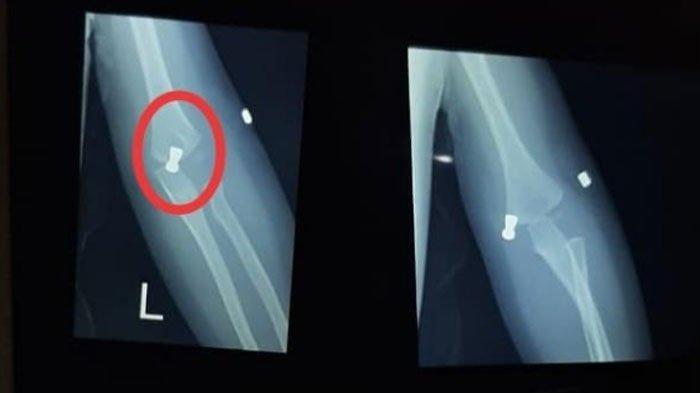

Pria yang akrab disapa Rahman ini juga menjelaskan, berdasarkan hasil rontgen, posisi peluru nyasar itu menembus kulit KH.

Hasil rontgen KH yang menjadi korban peluru nyasar, Rabu (5/8/2020).

Namun untung saja kata dia, tidak sampai menembus tulang.